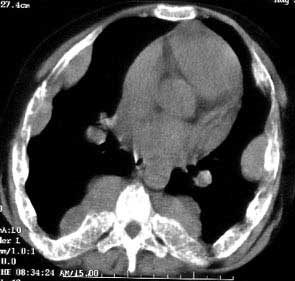

以下是引用jiajie在2004-12-10 22:14:53的发言:[br]多发性肋骨骨质疏松,[br][br]麦粒状及筛孔状骨质破坏,[br][br]髓腔膨胀皮质变薄,[br][br]骨旁多发软组织肿块,[br][br]考虑恶性病变,支持肋骨多发性骨髓瘤。

以下是引用pujunzhi在2008-7-3 21:21:00的发言:[br]支持地中海贫血伴髓外造血可能性大,需与多发性骨髓瘤、淋巴瘤等鉴别。